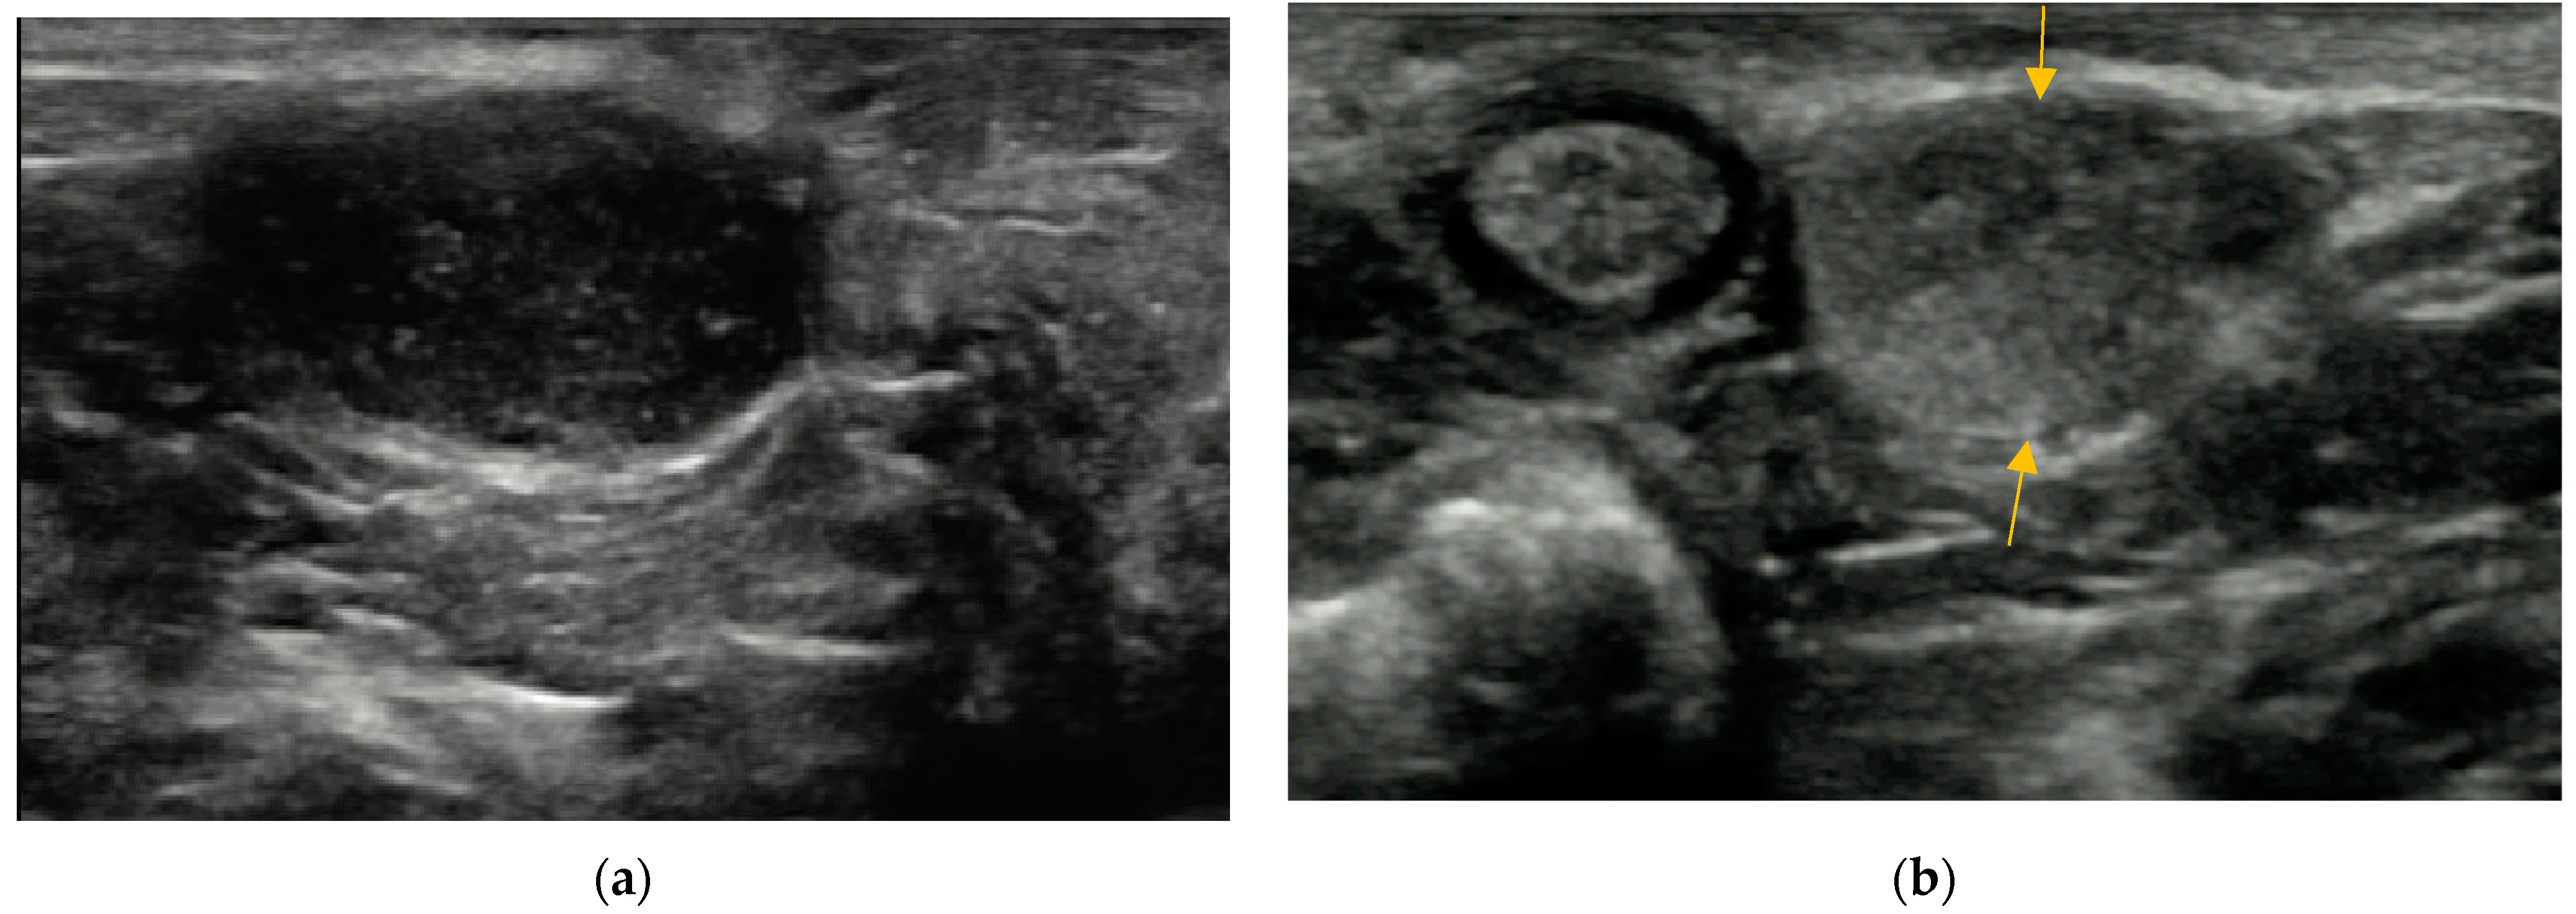

2.4.3. Wall of Anal Sacs

3.4. Wall of Anal Sacs